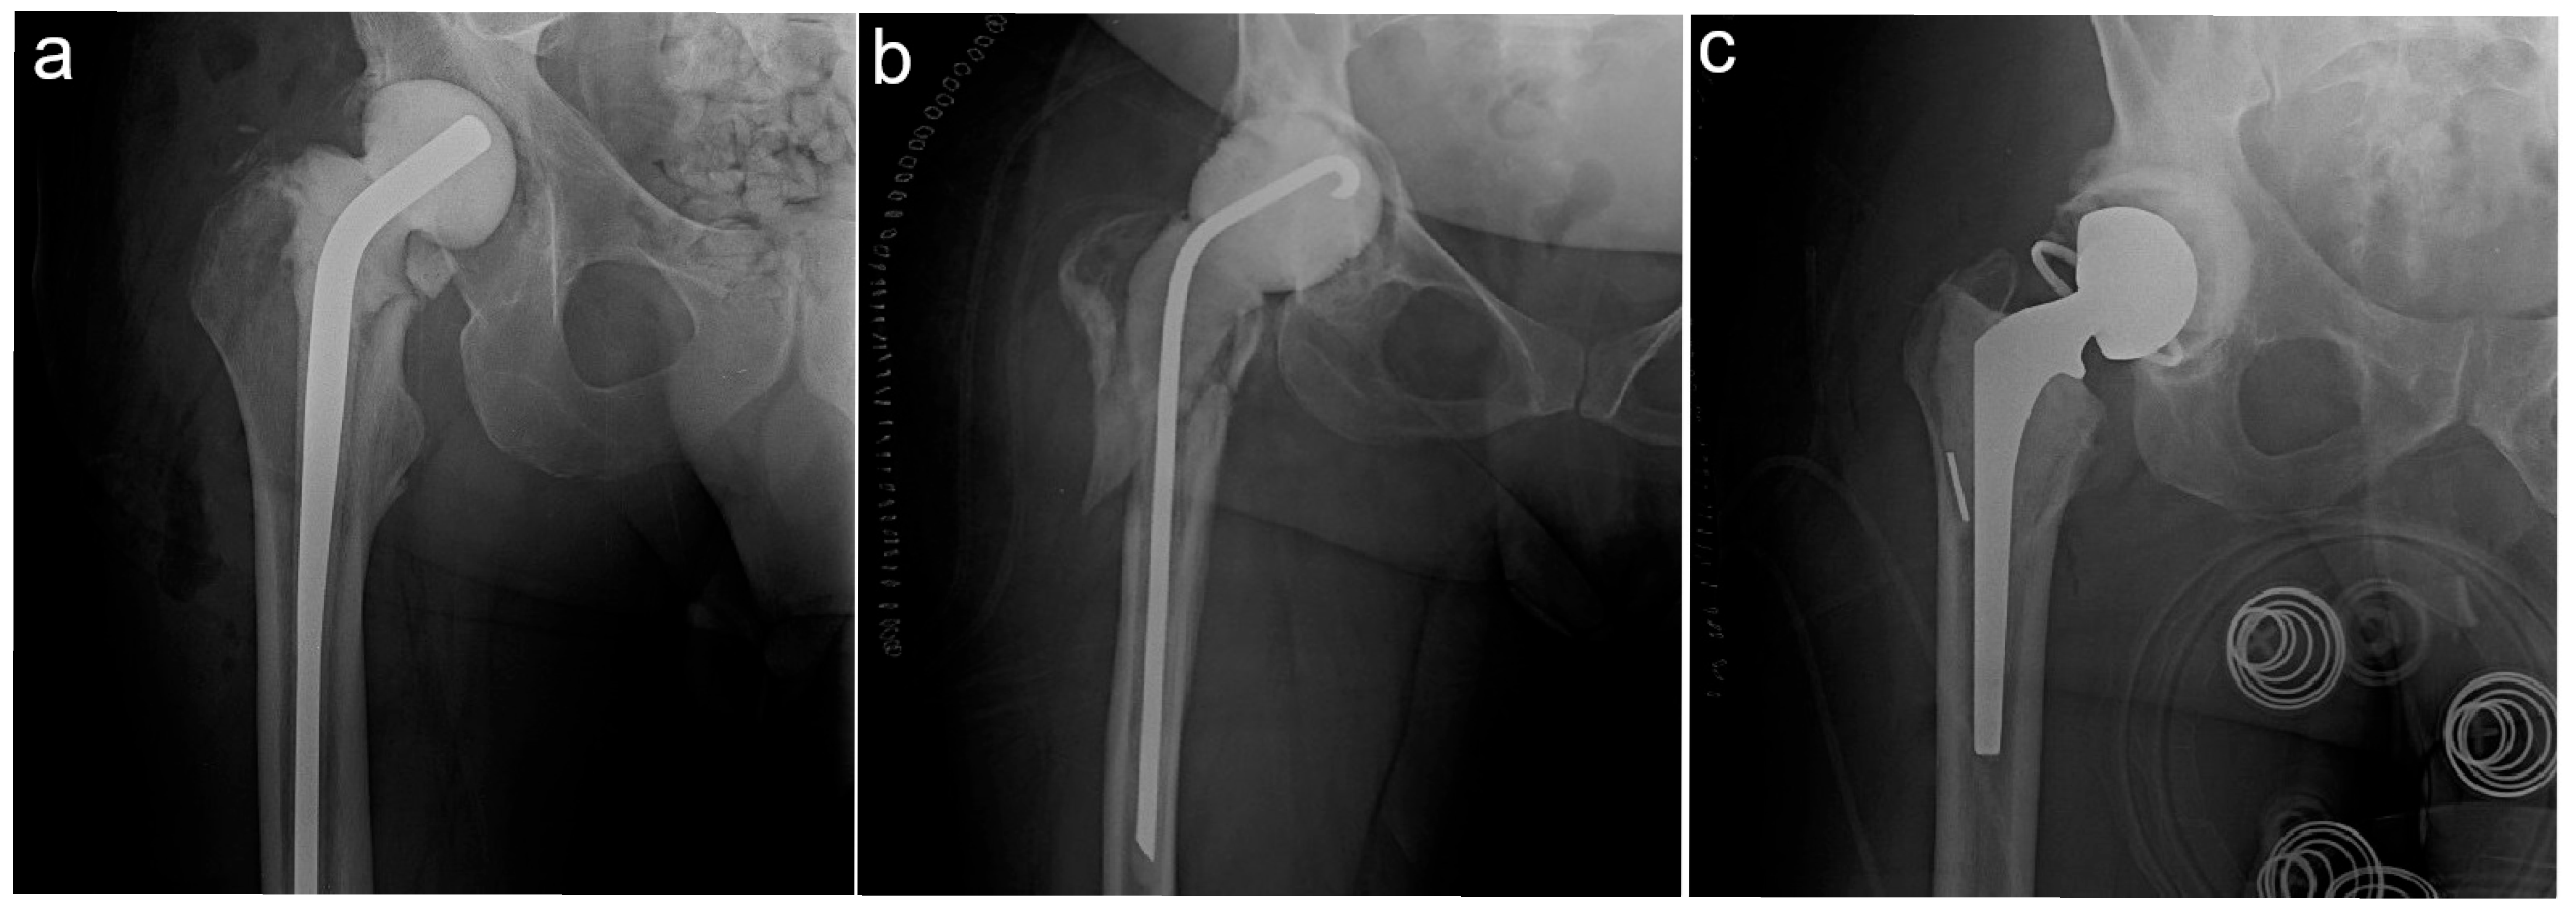

2.3. Assessment of In Situ Spacer Complications